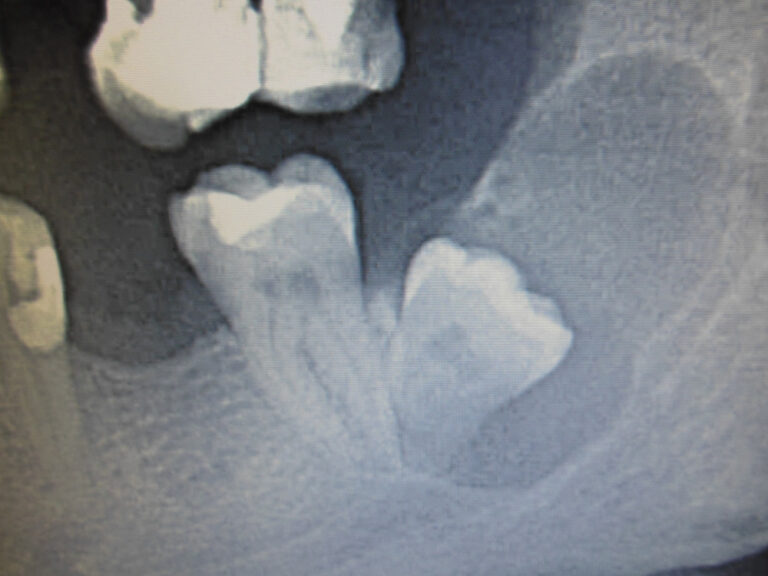

Ortodoncja CBCT

Leczenie chirurgiczno-ortodontyczne wad zębowych z zastosowaniem tomografii spiralnej CBCT w naszej klinice.